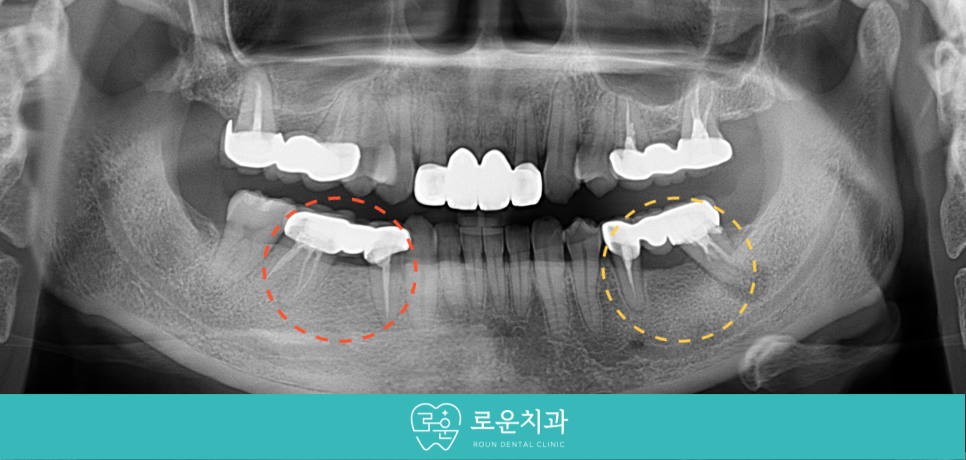

이어 두 번째 작은 어금니(#35)의

재 신경치료를 진행하였는데요.

아래턱 왼쪽 두 번째 큰 어금니(#37) 발치 후

2달쯤 경과하였을 때

임플란트 식립이 가능한 환경이 되었다고 판단하여

식립을 도와드렸습니다.

먼저 기존 보철물 제거 후

상실된 부위에 안정적인 위치와

추후 보철물을 고려하여

정확한 방향으로 임플란트 식립을 진행하였으며,

첫 번째 큰 어금니(#46)의 재 신경치료 후

첫 번째 작은 어금니(#44)와 함께

크라운 수복을 도와드렸습니다.

식립 후 임플란트가

주변 잇몸뼈와 단단히 결합되었을 때

양옆의 크라운 보철물과 같은

지르코니아로 최종 보철물 제작을 도와드리면서

치료를 마무리해 드렸습니다.

[치료 전 -> 후]